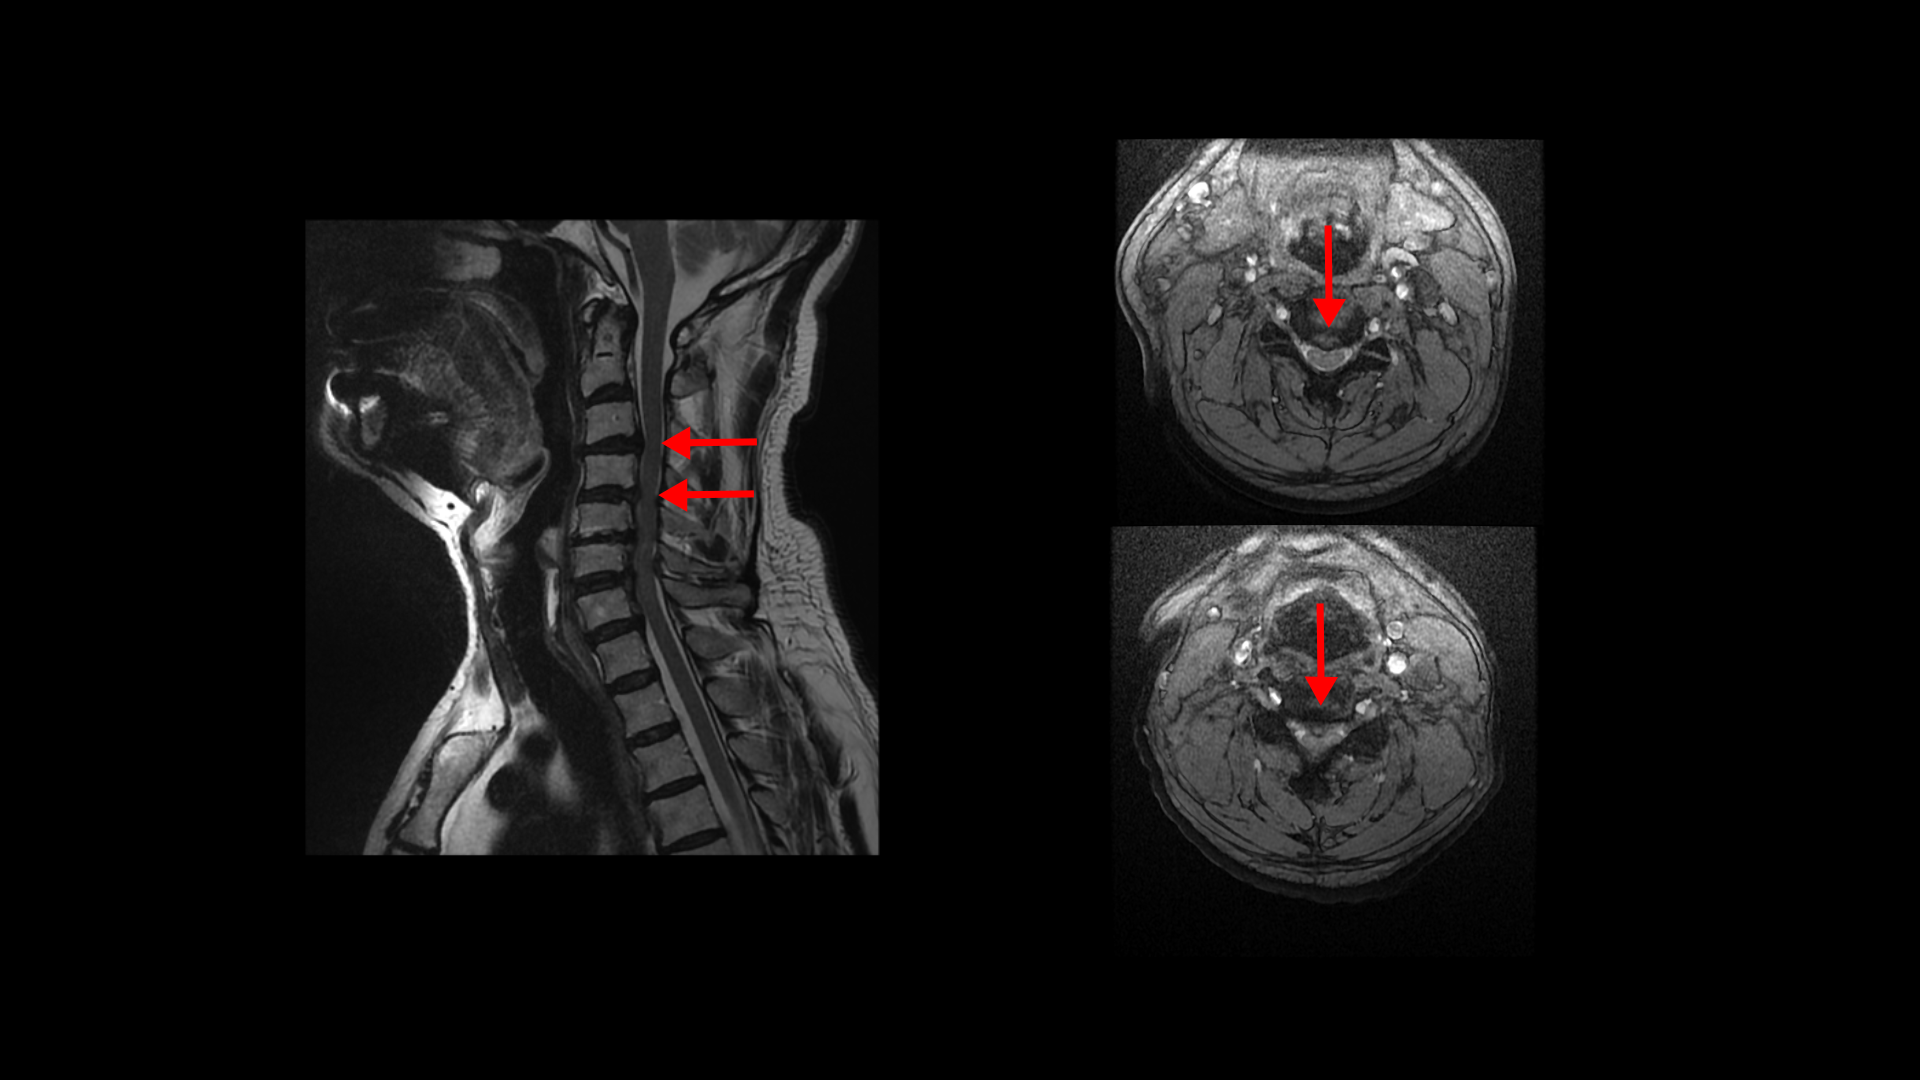

팔의 통증과 저림, 숟가락질과 젓가락질이 어려운 경추척수증 환자분의 MRI 상태 및 증상은?

이 환자분의 목에 7~8년 전에 심한 목디스크 파열이 발생하였습니다. 오른 팔이 극심하게 아팠고 디스크 파열이 너무 심하고 척수증까지 있어서 수술 권유를 받았으나 주변의 만류로 수술은 받지 않고 물리치료와 신경 주사만 맞으면서 버티셨습니다.

이분 MRI에서 보시다시피 전체적으로 목의 한마디만 제외하고 여러 마디가 다 안 좋습니다.

목의 3번 4번과 4번 5번에는 가운데 쪽으로 디스크 돌출이 있고

5번 6번 문제가 제일 심각한데, 가운데 우측으로 목디스크 파열이 심하게 있습니다.

오른쪽으로 보시다시피 신경 나가는 길이 디스크와 협착으로 많이 막혀 있고 척수 신경에는 경추척수증, 즉 척수신경의 손상이 보입니다.

6번 7번과 7번 흉추 1번 디스크도 가운데로 밀려 나와있습니다.

이 환자분의 오른쪽 팔의 통증과 젓가락질이 안 되는 증상은 척수증보다는 목디스크 파열과 경추협착으로 인한 증상으로 보입니다. 즉 척수증은 있지만 척수증 관련된 증상은 없어 보입니다.